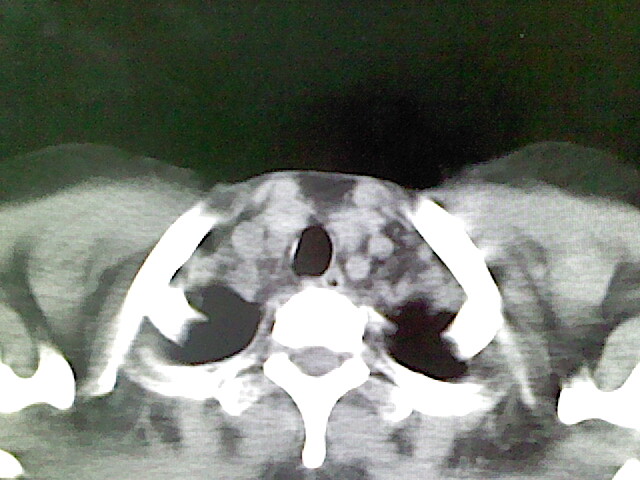

女,52岁,咳嗽,咳痰多日

左下肺陈旧纤维索条!

左肺舌段炎性改变

我见过几例,为炎症后纤维条索

慢性炎症后改变

考虑慢性炎性病灶粘连牵拉改变。

左肺舌叶纤维锁条病变。

左肺上叶下舌段炎症并局部胸膜反应。

左肺舌叶纤维索条影。

左肺舌叶段陈旧性病变

左肺舌段炎性反应。片子的质量太不好了。

左肺舌段炎性

炎性改变

左肺舌叶纤维索条影